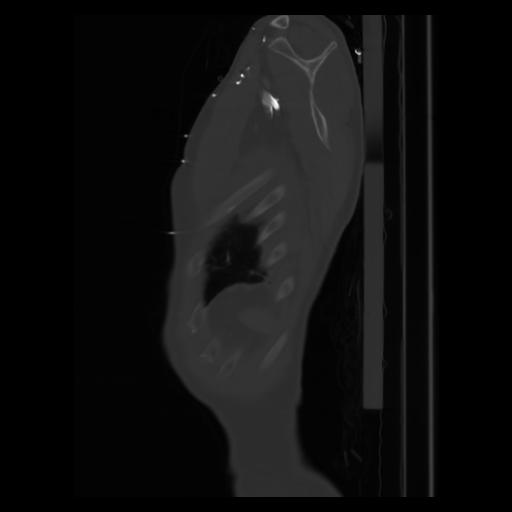

30 CUERPO,CE,Sagittal,3.000,CUERPO,Sagittal,